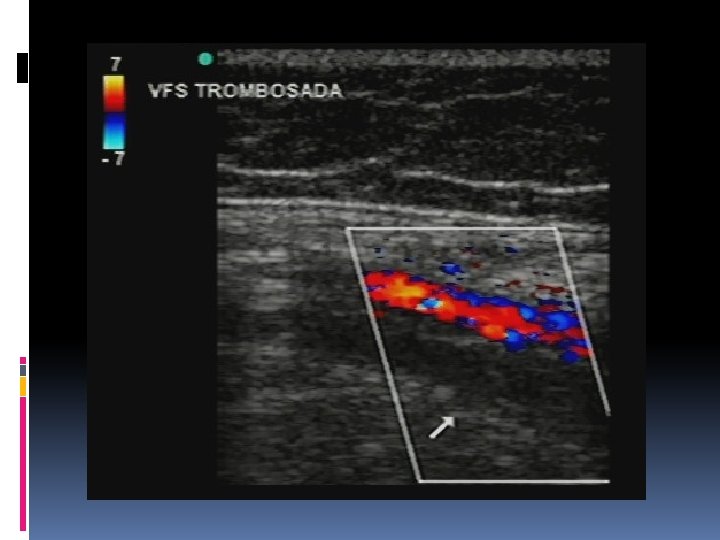

Estudio ecográfico. El objetivo del Doppler venoso es confirmar la permeabilidad vascular, identificar el tipo de insuficiencia venosa (profunda, superficial y/o de comunicantes), determinar los puntos de reflujo/entrada y realizar el mapeo venoso (expresión gráfica del estudio).

Criterios de diágnóstico de reflujo anormal en la venas De acuerdo consenso de la Unión internacional de Flebología publicado en las Guías de Manejo del Foro Venoso Americano, los criterios actuales son: Reflujo mayor de 1 segundo para la vena femoral y poplítea. Reflujo mayor de 0. 5 segundos para las demás venas del sistema venoso profundo y para todas las venas del sistema venoso superficial. Reflujo mayor de 0. 5 seg y diámetro mayor de 0. 35 cm para las venas perforantes, con la precaución que sólo se deben considerarse a tratar aquellas venas perforantes que se encuentren cercanas a una úlcera cicatrizada o activa; es decir, pacientes en estadío C 5 y C 6 de la clasificación de CEAP. Dr. Álvaro Cruz Mézquita.